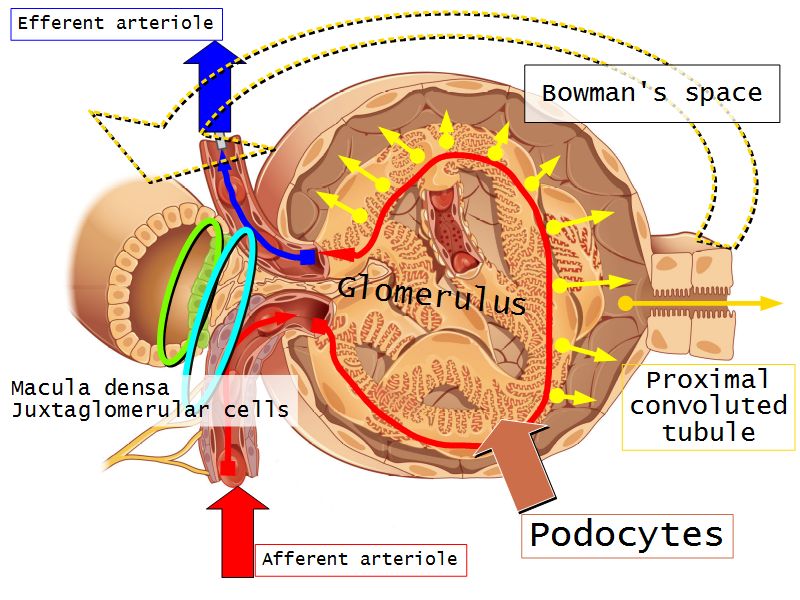

Renal corpuscle

- Tuft of capillaries

- grow into

- Blind end of nephron

- Several layers of epithelium

- Two sides

- Vascular pole

- Tubular pole

Blood flow

- Efferent arteriole

- Smooth muscle in media

- Capillaries

- Fenestrated

- Afferent arteriole

- Smooth muscle in media

Epithelium layers

- Capillary endothelium

- Visceral layer of epithelium

- Podocytes

- Resting on glomerular basement membrane

- Capsular space

- Parietal layer of epithelium

- Simple squamous epithelium

Juxtaglomerular complex

Area where distal convoluted tubule return to glomerulus and pass through the notch between the afferent and efferent arterioles. Modification of the wall of the tubule and afferent arteriole and presence of specialised cells in the connective tissue.Modifications

- Distal convoluted tubule

- Macula densa

- Narrow epithelial cells

- Nuclei densely packed

- CT cells

- Laci cells

- Similar to mesangial cells

- Afferent arteriole

- Modified smooth muscle cells

- Juxtaglomerular cells

- Secretory function